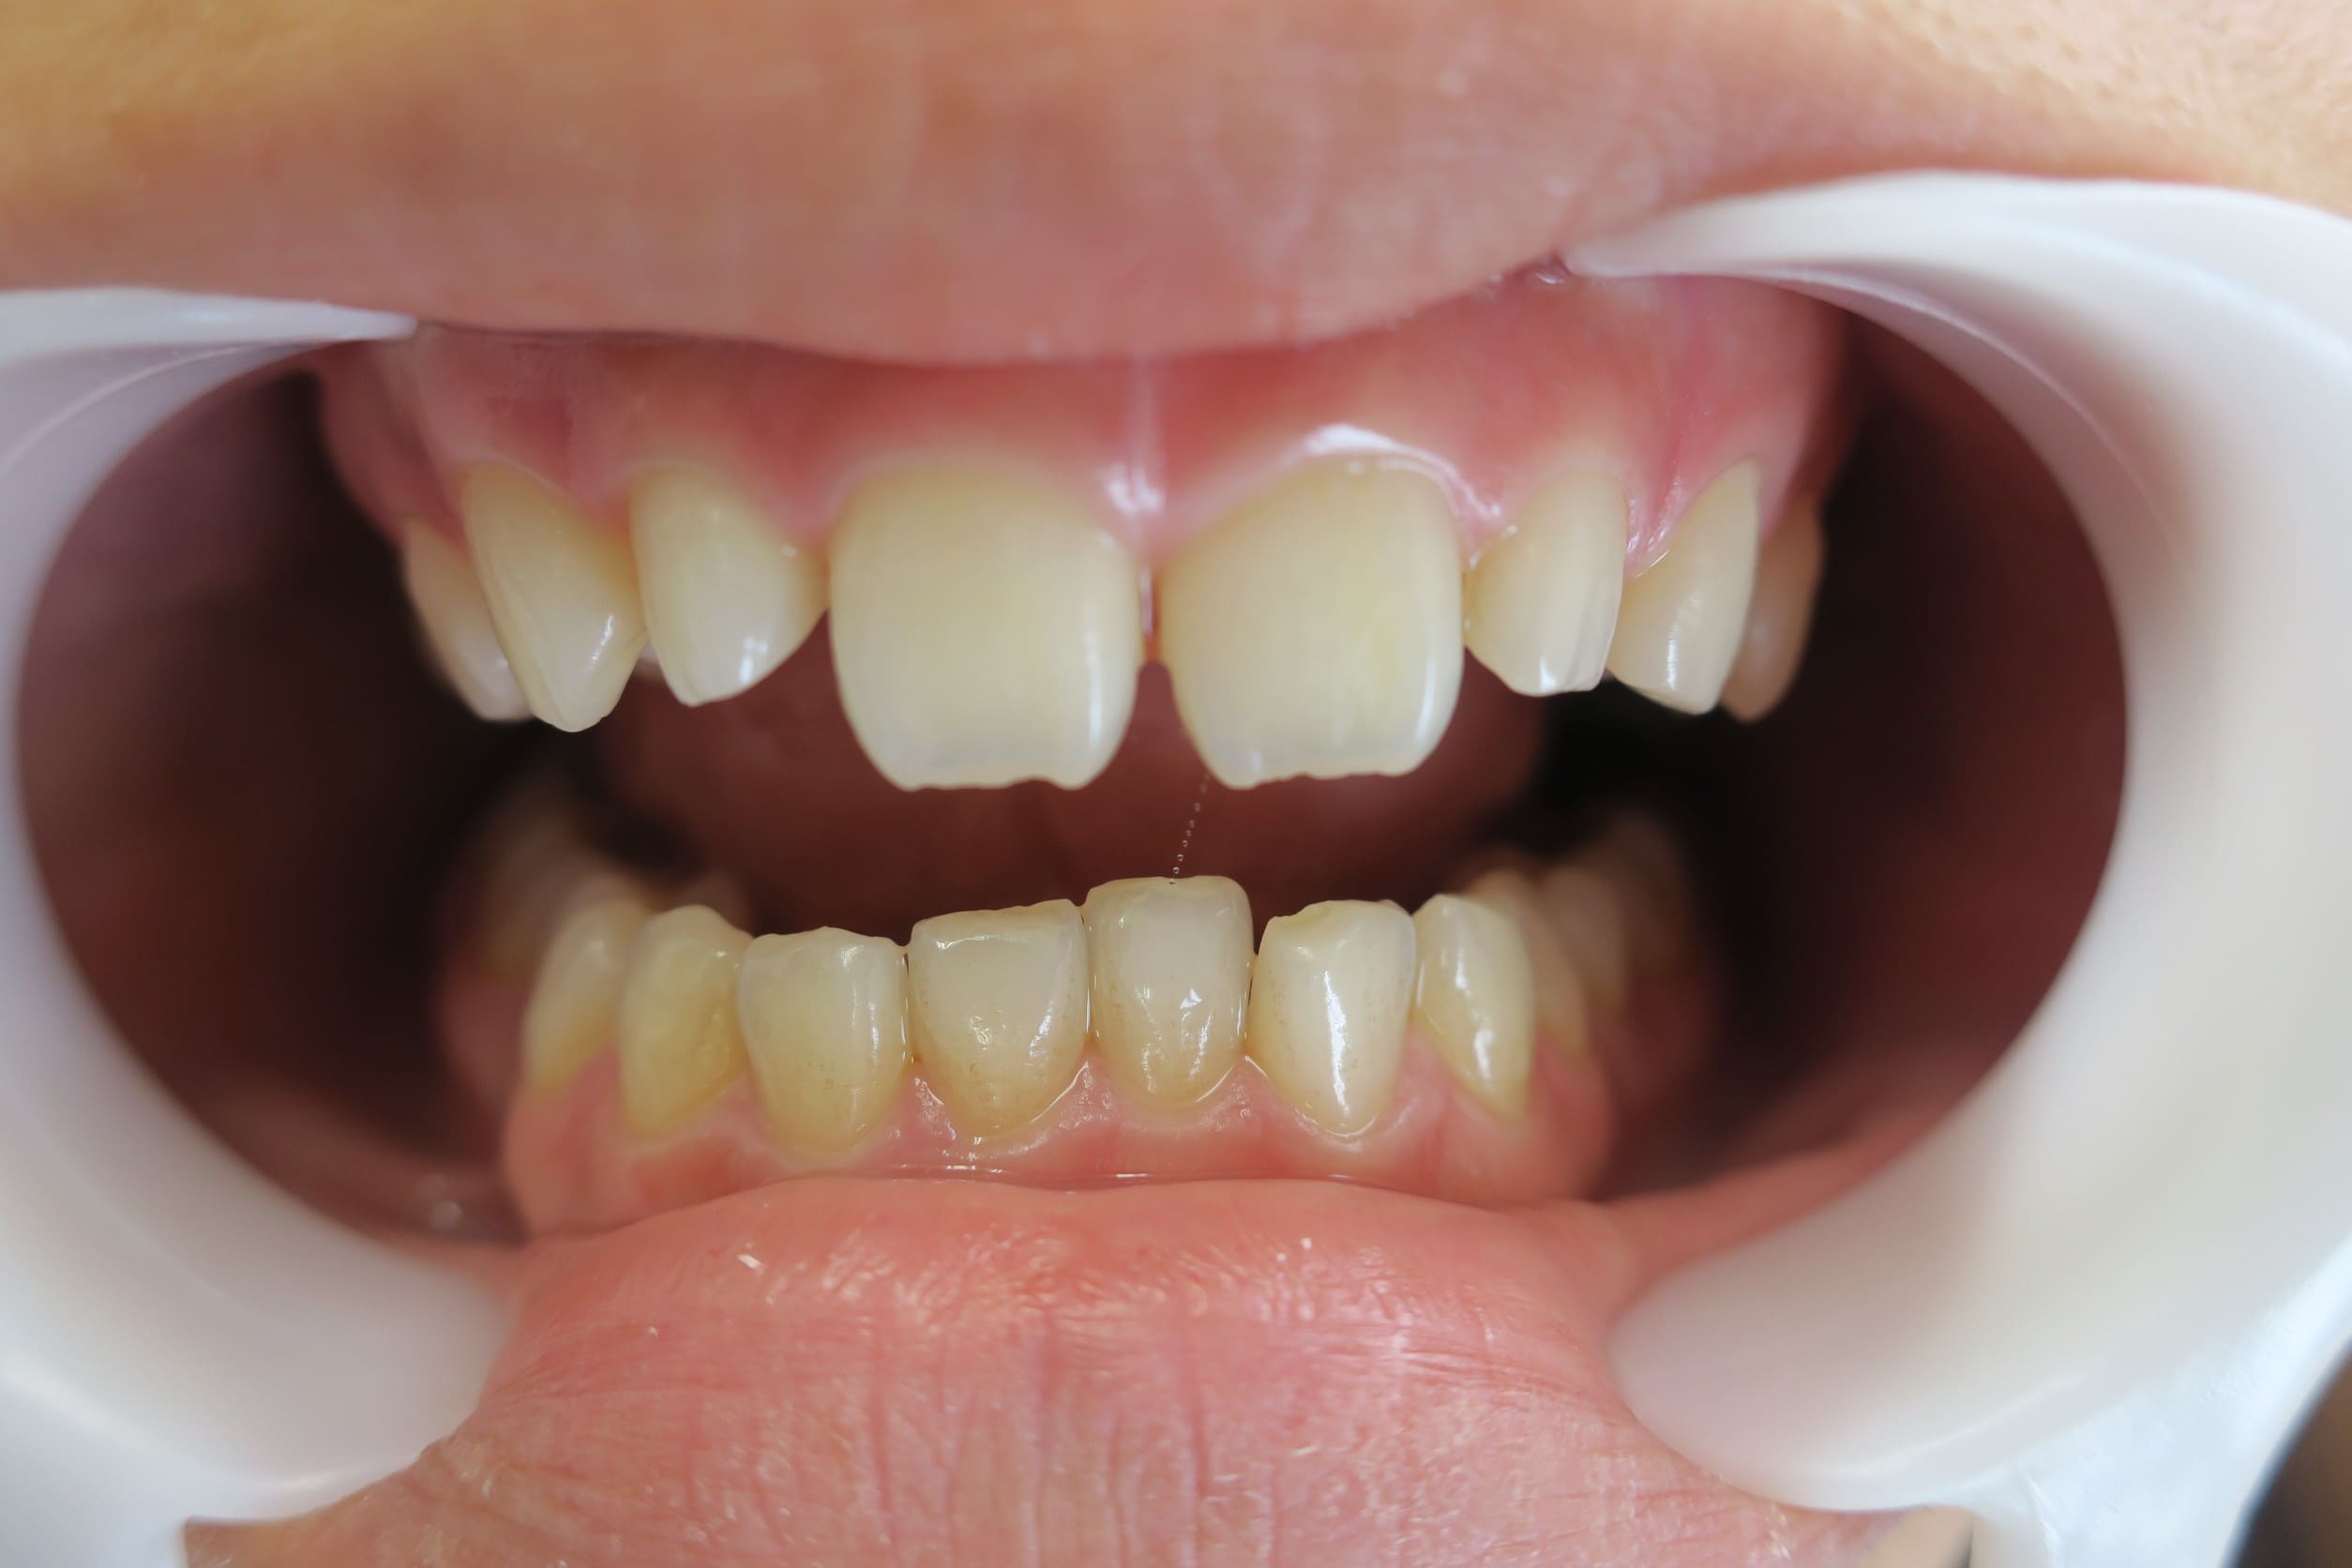

藤沢デンタルオフィスのホワイトニング術前

藤沢デンタルオフィスのホワイトニング術後

藤沢デンタルオフィスのホワイトニング術前 藤沢デンタルオフィスのホワイトニング術後

術前

術後